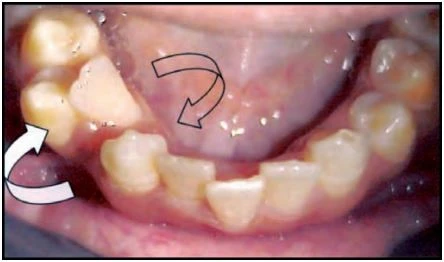

Thuật ngữ này dùng để chỉ những trường hợp hai răng bị đổi chỗ cho nhau, chẳng hạn răng nanh đổi vị trí cho răng cửa bên.